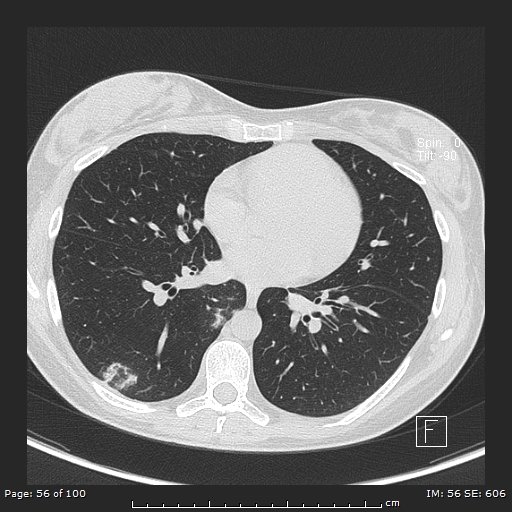

Atoll Sign (Reverse Halo Sign)

• Atoll = circular island with water in the middle (looks like a doughnut)

• Central ground glass opacity with consolidative/enhancing rim

• DDx:

• Cryptogenic organizing pneumonia - main cause

• Fungal pneumonia

• Wegeners (granulomatosis with polyangitis)

• Sarcoid or TB

• Others